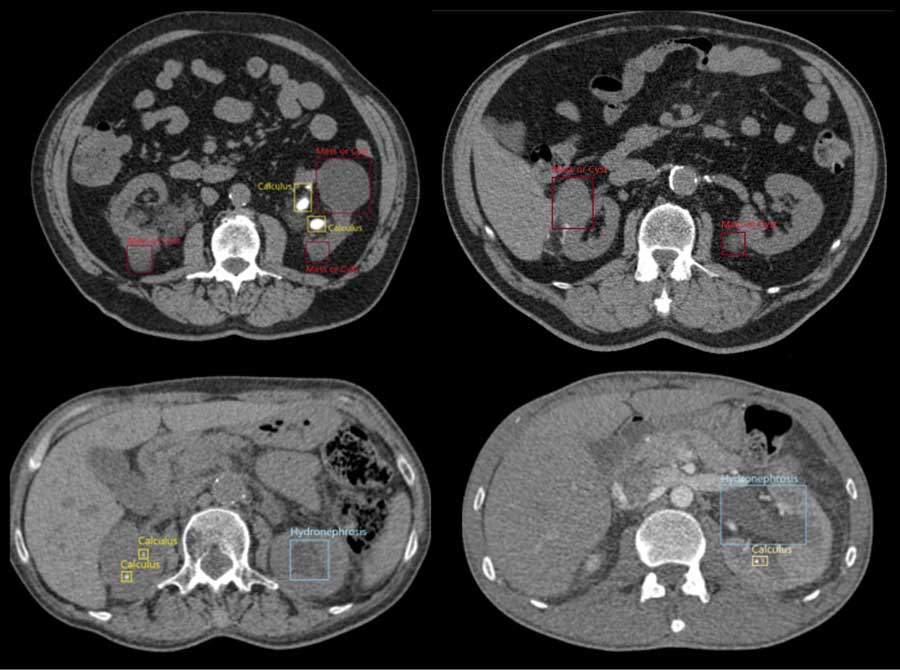

Fig. Detection of abnormalities using AI

The majority of products related to AI diagnosis focus on preventing serious diseases from being overlooked and are used to diagnose a single type of disorder. By contrast, MaestroAI is able to comprehensively detect all abnormal areas within the target organ. This supports a broader range of medical diagnostics and helps address the issue of shortage of doctors by ensuring greater efficiency in diagnosis.